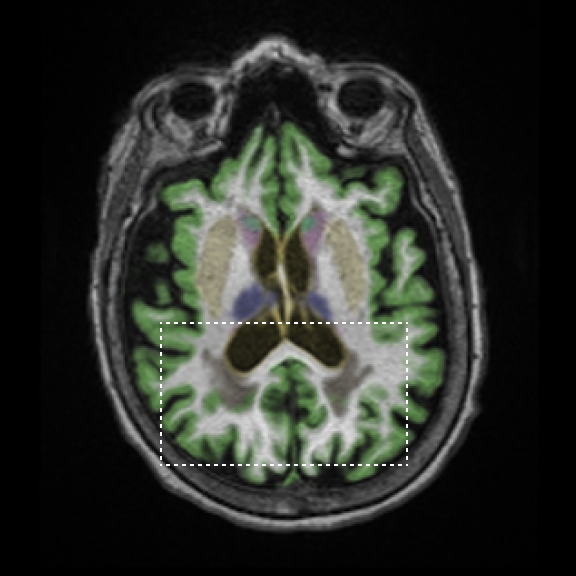

Monitor brain health over time

Track changes in brain volume with reliable quantitative data, enabling earlier intervention and more informed care.

Track across scanners

SwiftMR and SwiftSight minimize scanner variability, enabling longitudinal tracking across vendors and models.

Track brain volumetry results over time